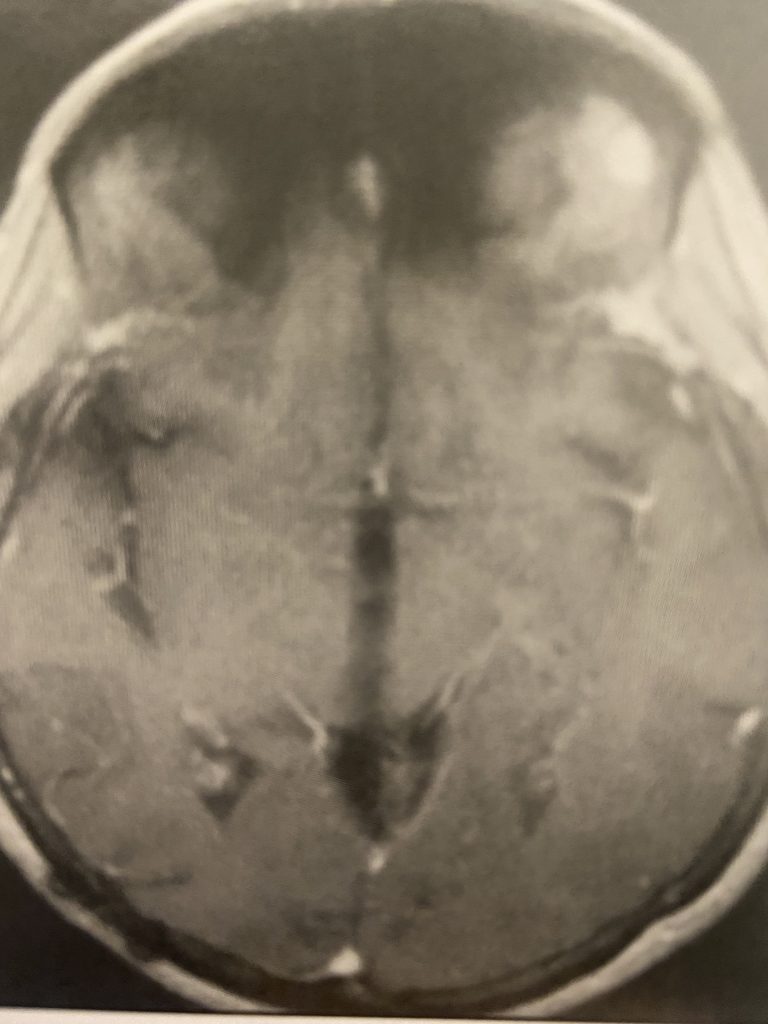

Figure 3

Postoperative post contrast axial MRIs demonstrating complete removal of the tumor with resolution of the hydrocephalus.

Subsequently, the hydrocephalus resolved and the patient did not require shunting. Her pre-operative symptoms all resolved. Follow up MRI demonstrated complete removal of the tumor.